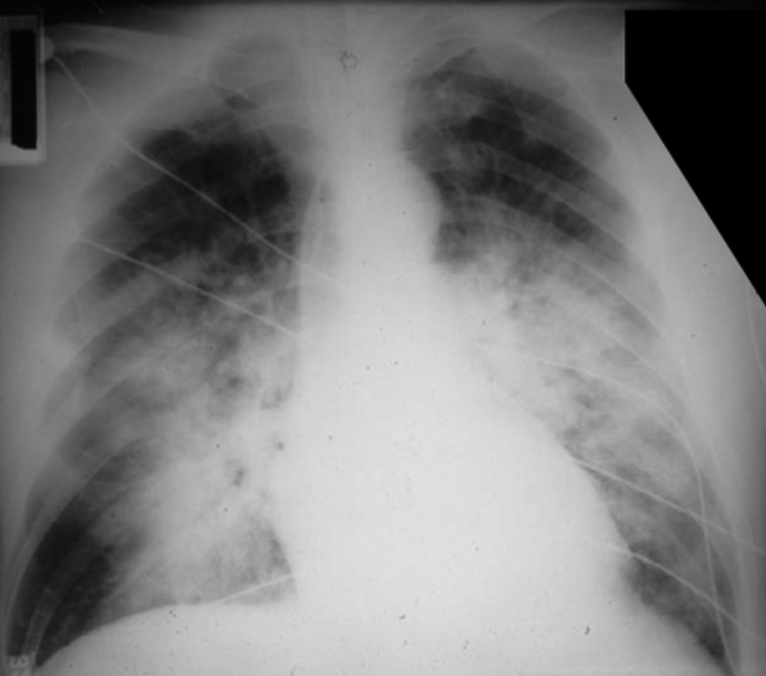

江苏一位51岁的女士感染流感后硬扛了10多天,拖成了重症肺炎,CT一查是大白肺,随时有生命危险。

就像开篇第一个新闻里的那位女士一样,五十多岁、有基础疾病,得了流感后硬是扛了10多天,晕倒后才发现是重症肺炎。肺全白了,专业一点讲是弥漫性炎症性肺损伤/急性呼吸窘迫综合征。疾病发展到如此严重的程度,临床检查肯定是可以发现些异常的,比如弥漫性湿啰音、呼吸困难、呼吸过速、心动过速、发绀、动脉血氧饱和度低等等。

注:封面图片来源UTD临床顾问